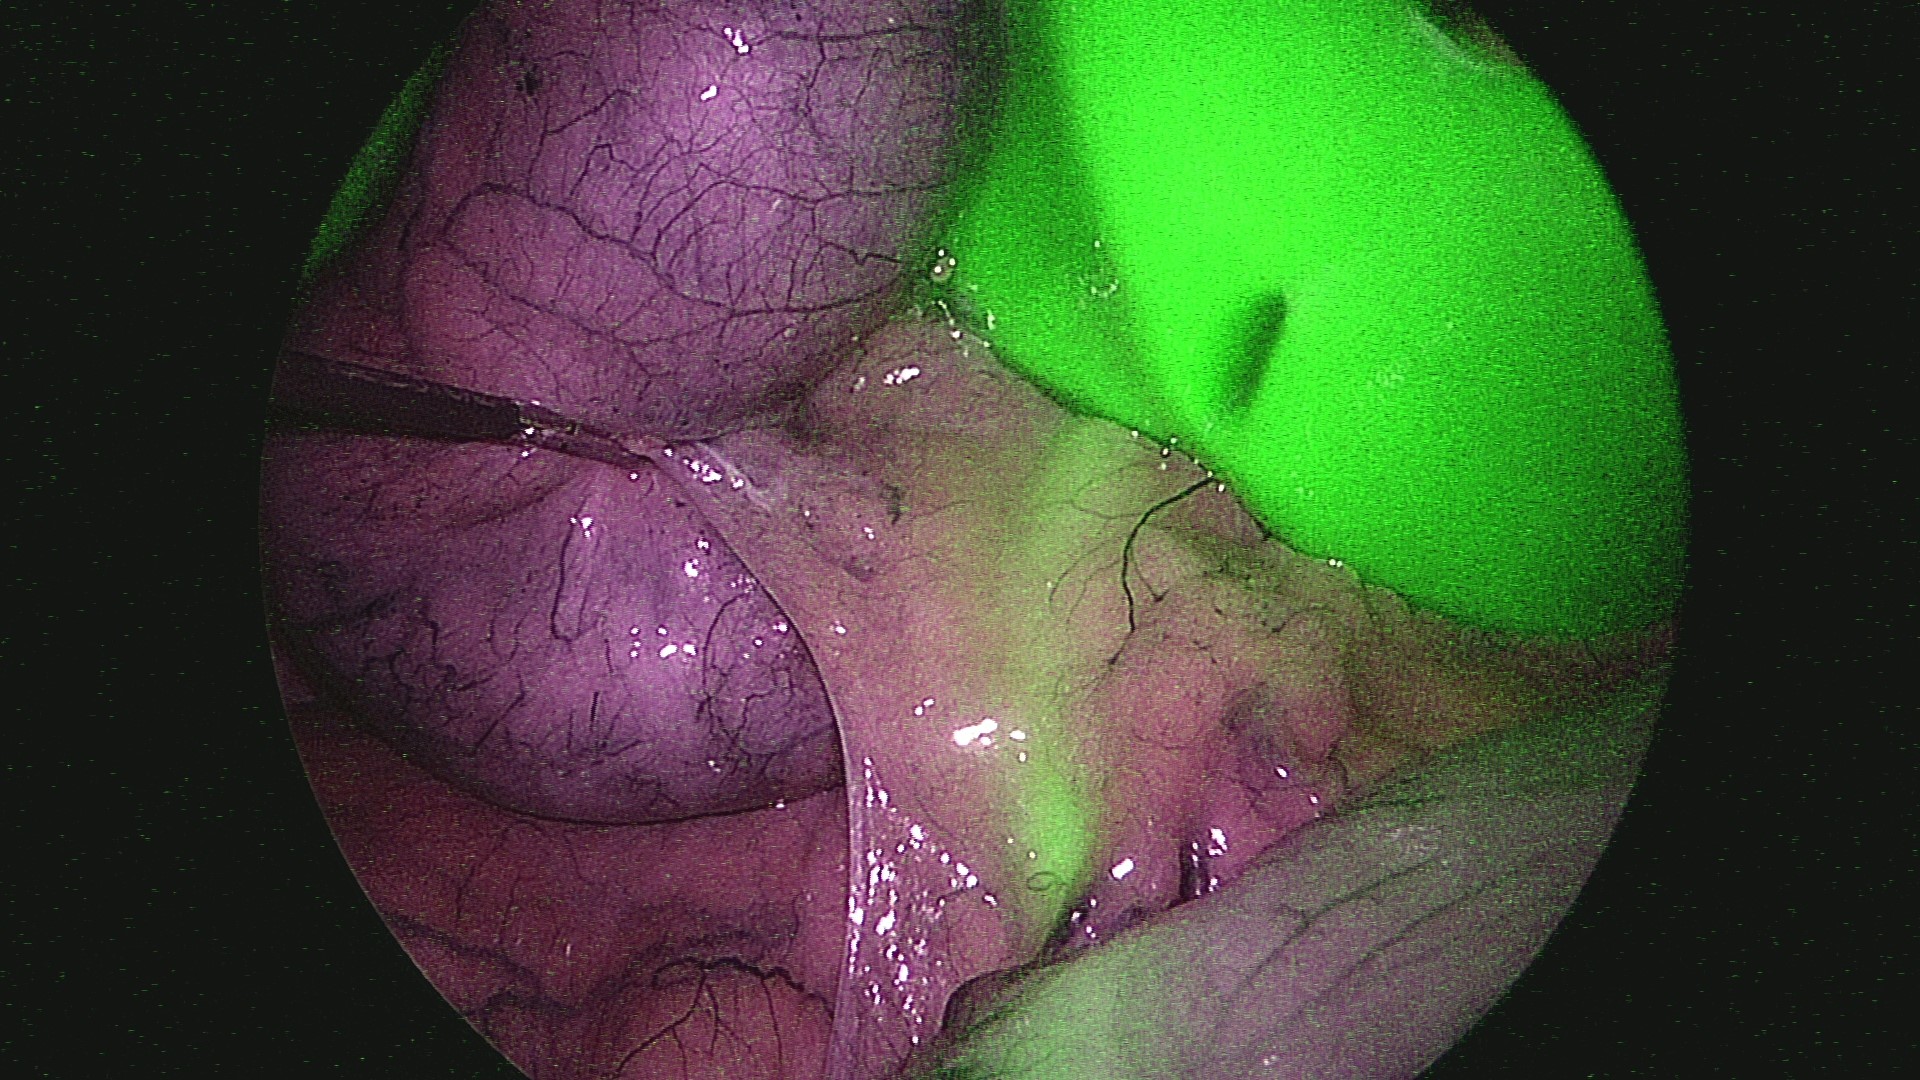

ICG螢光腹腔鏡影像手術系統

螢光腹腔鏡影像系統是利用靛氰綠 (Indocyanine green, ICG)藥物特性,能反射出光源的紅外線,再經過影像系統的處理就是我們看到的螢光圖案,透過螢光及染色,清楚辨認手術界線。